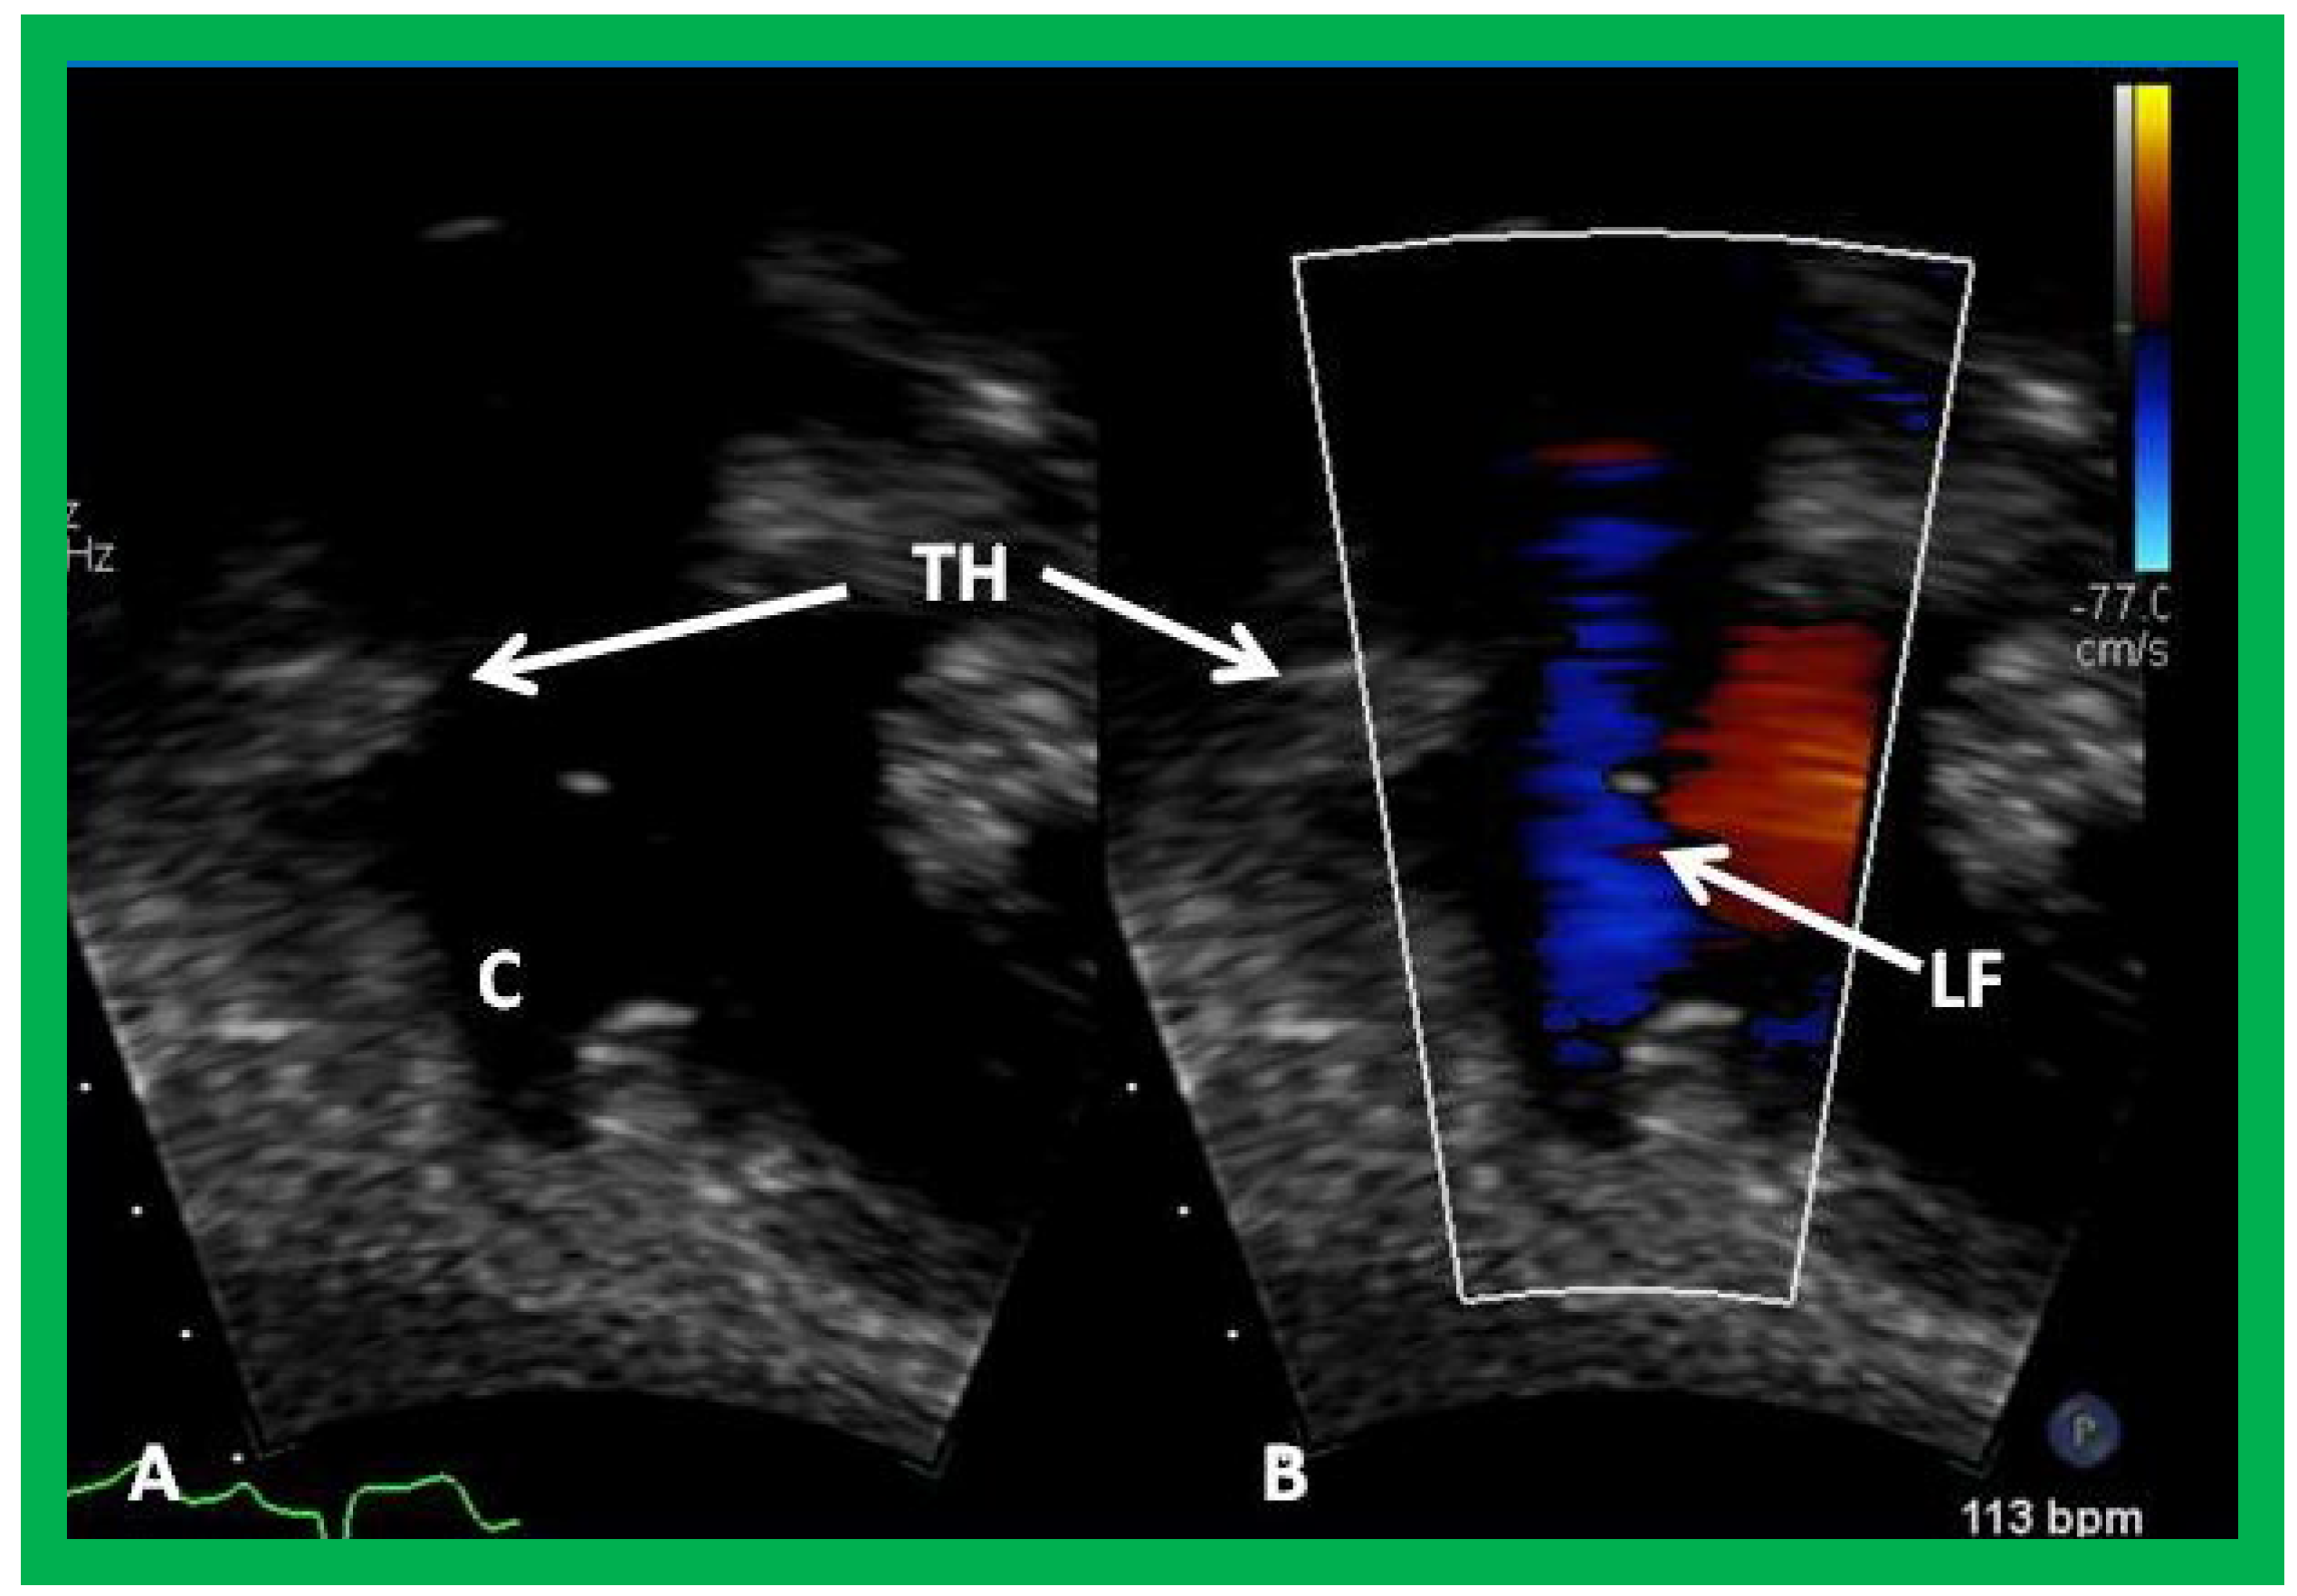

In patients who had an aorto–pulmonary shunt (most commonly modified Blalock–Taussig), the shunt may be visualized by color flow imaging (Figure 19), although it is difficult to image it only by 2D. High Doppler flow velocities across the shunt are normally recorded (Figure 20), and they reflect the systolic pressure difference between the aorta and PAs. Low Doppler flow velocities across the shunt, however, may indicate high PA pressures. The flow into branch PAs can easily be demonstrated by color flow Doppler imaging (Figure 19B). Flow acceleration in the branch PAs is usually seen (Figure 21) and is of no concern. However, high flow velocities may indicate branch PA stenosis.

Figure 19. Selected video frames from suprasternal notch view demonstrating proximal shunt (PS) by color flow imaging (A). In a slightly different view, (B), the flow from the distal shunt (DS) into right (RPA) and left (LPA) pulmonary arteries is shown.